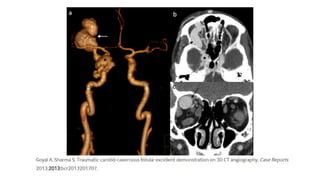

Imaging modalities – CT/CT Angio

• Proptosis

• Expansion of the cavernous sinus

• Superior ophthalmic vein

• Enlargement of extraocular muscles,

• Any associated skull fractures.